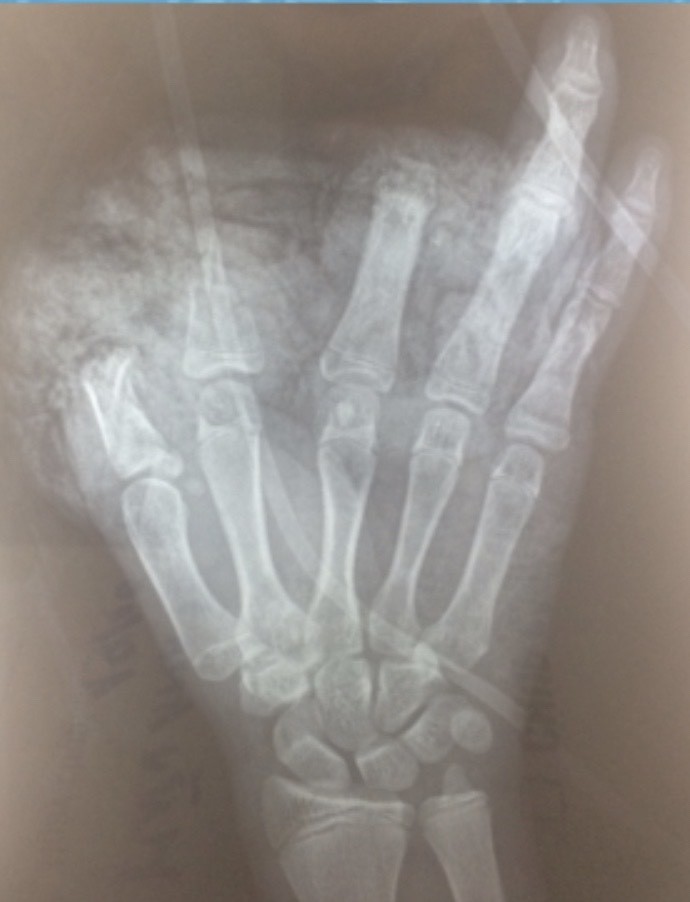

Hình ảnh X-quang bàn tay trái của bé T. (Ảnh: BVCC) |

Bé N.H.A.T. 14 tuổi, sống ở phường Trang Hạ, Thị xã Từ Sơn, tỉnh Bắc Ninh vào Bệnh viện Hữu nghị Việt Đức trong trạng thái tỉnh, huyết động ổn định, vùng hàm mặt, ngực, bụng có nhiều xây xát; mắt trái bị rách lớp mi trên, cương tụ kết mạc. Không chỉ vậy, bàn tay trái của bé bị dập nát, cụt chấn thương ngón 1,2,3; vết thương mu tay và gan tay dài 10cm, da gan tay bị lóc cùng nhiều dị vật đen, bẩn.

ThS. BS. Đoàn Lê Vinh - Khoa Phẫu thuật Chấn thương Chung, Bệnh viện Hữu nghị Việt Đức - cho biết: Ngay sau khi tiếp nhận bệnh nhi, các bác sĩ đã tiến hành bơm rửa, làm sạch vết thương nhiều lần, cắt lọc sạch vết thương cho bé. Bé đã được được phẫu thuật cấp cứu cắt lọc sửa mỏm cụt ngón 1,2,3; xử lý vết thương phần mềm gan bàn tay, mu bàn tay và nhiều vị trí thương tổn khác. Ca phẫu thuật diễn ra trong 1 tiếng.